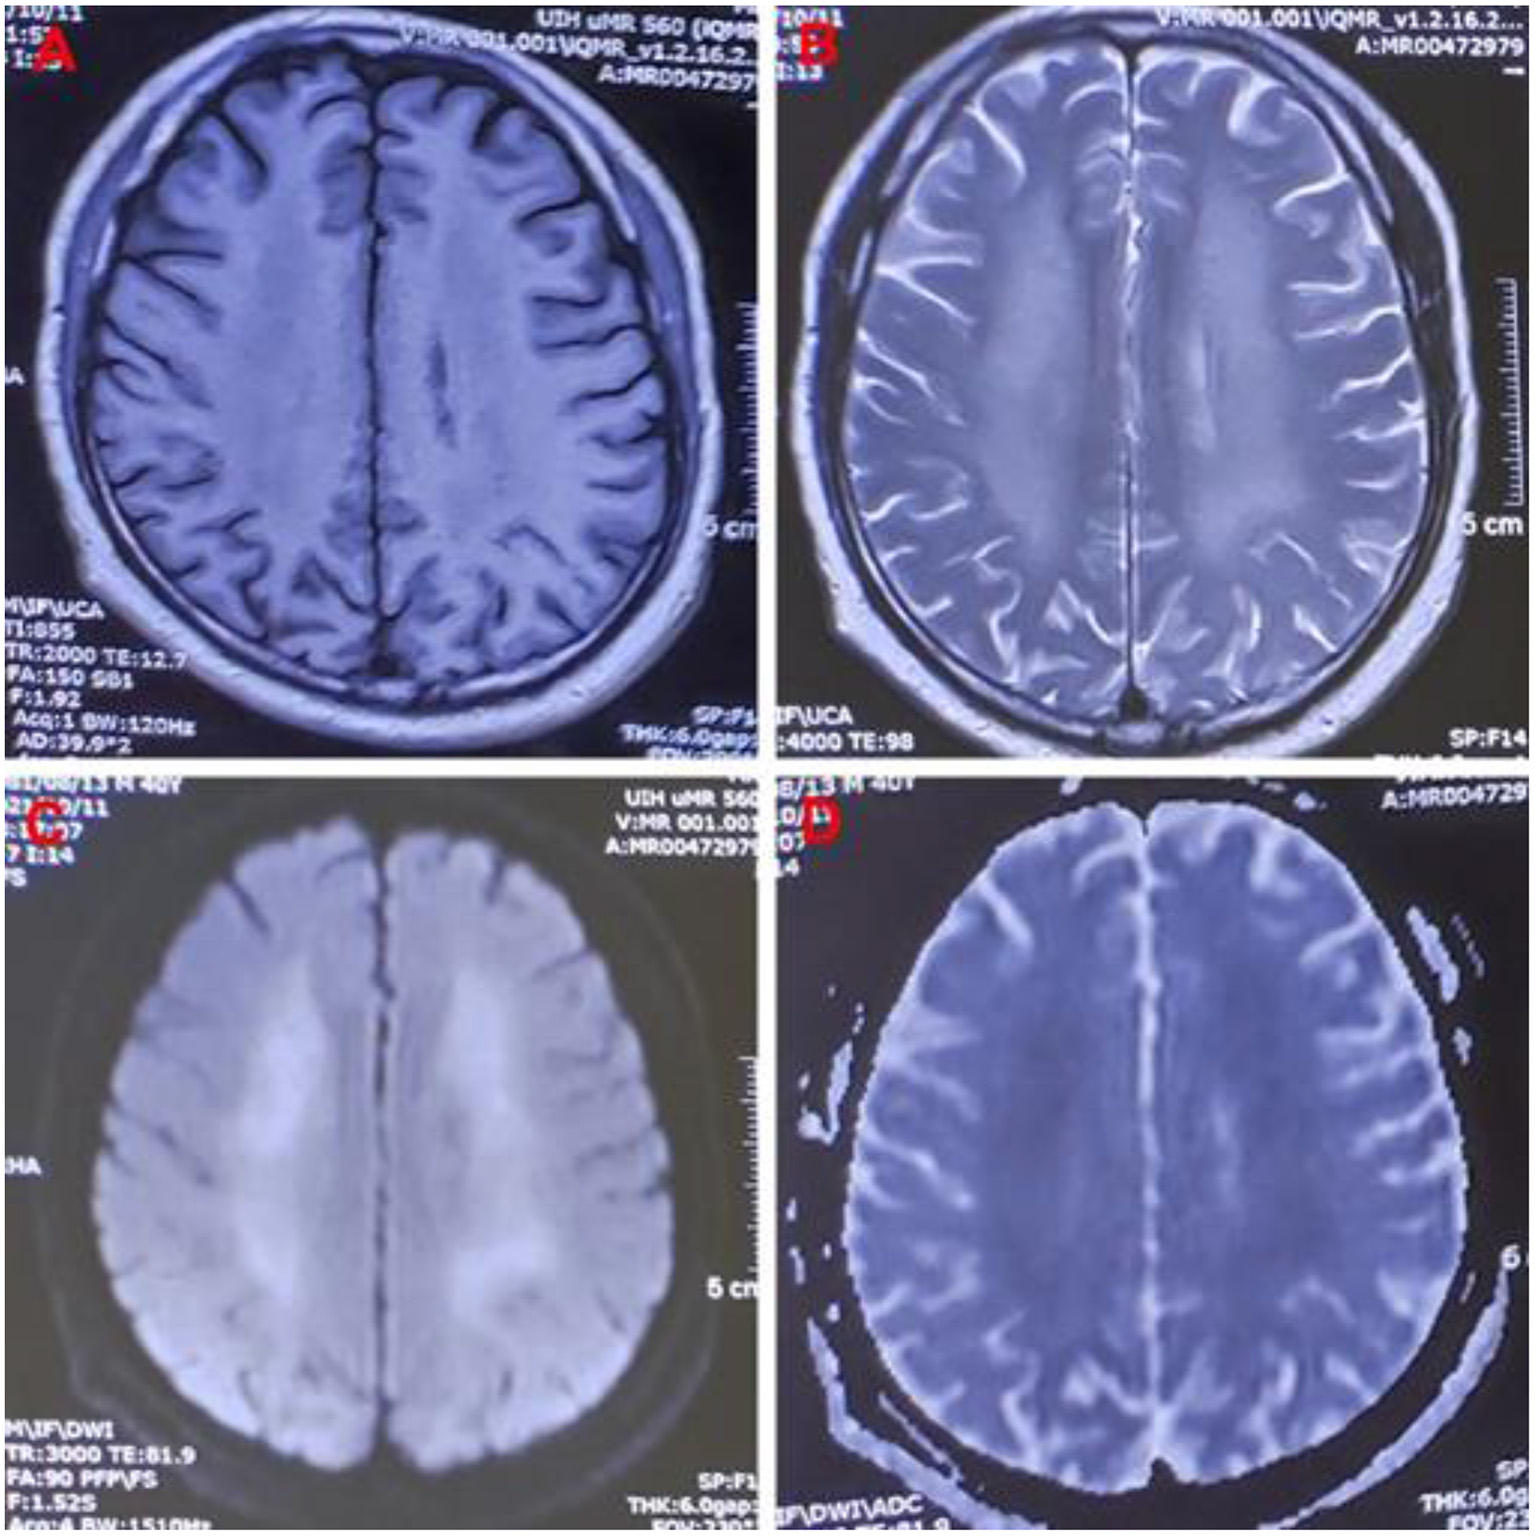

One month later, the patient complained of memory loss and slower motor responses. Electromyographic results were normal. Brain magnetic resonance imaging (MRI) showed symmetric abnormal signals [hypointensities on T1-weighted image (T1-WI) and hyperintensities on T2-weighted image (T2WI) and diffusion-weighted image (DWI)] in both the basal ganglia, corona radiata region, centrum semiovale, and thalamus; thus, a diagnosis of delayed encephalopathy was considered (Figure 1). Four months after exposure, central nervous system symptoms showed slight improvement, and brain signal abnormalities also improved. The patient's laboratory test results are shown in Table 1.

Figure 1

Images of a 40-year-old man exposed to 5-Bromo-2-nitropyridine. Magnetic resonance imaging 82 days after exposure showing abnormal signal intensity on (A) T1WI, (B) T2WI, (C) DWI, and (D) DWI/ADC in the bilateral cerebral hemispheres. T1WI, T1-weighted image; T2WI, T2-weighted image; DWI, diffusion-weighted imaging; DWI/ADC, diffusion-weighted imaging/apparent diffusion coefficient.

Hemolysis is the excessive destruction of erythrocytes, which can lead to anemia if not compensated for by adequate erythrocyte production. The causes of methemoglobinemia-related hemolysis include substance toxicity, glucose-6-phosphate dehydrogenase (G6PD) deficiency, and rapid or excessive overdose of MB (8, 13, 14). In our patient, methemoglobinemia caused histanoxia and muscle tissue damage; convulsions further exacerbated the muscle tissue damage, leading to rhabdomyolysis (7, 15). In this case, rhabdomyolysis and hemolysis occurred after 5-bromo-2-nitropyridine exposure, leading to a sharp increase in myohemoglobin and hemoglobin in the blood circulation and acute kidney injury. The patient showed marked improvement after treatment but developed slow movements and memory loss 2 months after exposure, and delayed encephalopathy was confirmed by MRI 82 days after exposure. The MRI showed symmetric hypointensities on T1WI and hyperintensities on T2WI and DWI in his basal ganglia, corona radiata region, centrum semiovale, and thalamus, which is similar to the findings in delayed encephalopathy after acute carbon monoxide poisoning (16). Some diseases can cause delayed encephalopathy (17), but in pyridine-compound poisoning, only a few cases involving toxic encephalopathy have been reported (18, 19). 5-bromo-2-nitropyridine-related delayed encephalopathy has not been previously reported, and the mechanism is unclear.